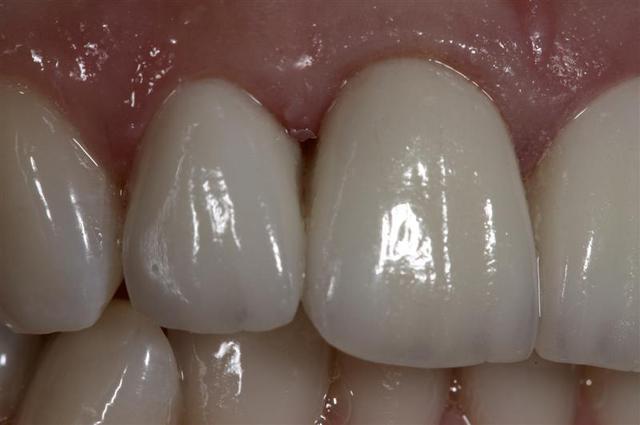

Quattres Empress 2...

et collées ...

J'ai mis Empress par habitude... ce sont des Emax.

oui taille définitive, vivante, collée au RelyX Transp

Sinon pour ton cas, bravo. Espérons que la papille de 21-22 vienne fermer le triangle noir disgracieux assez rapidement.